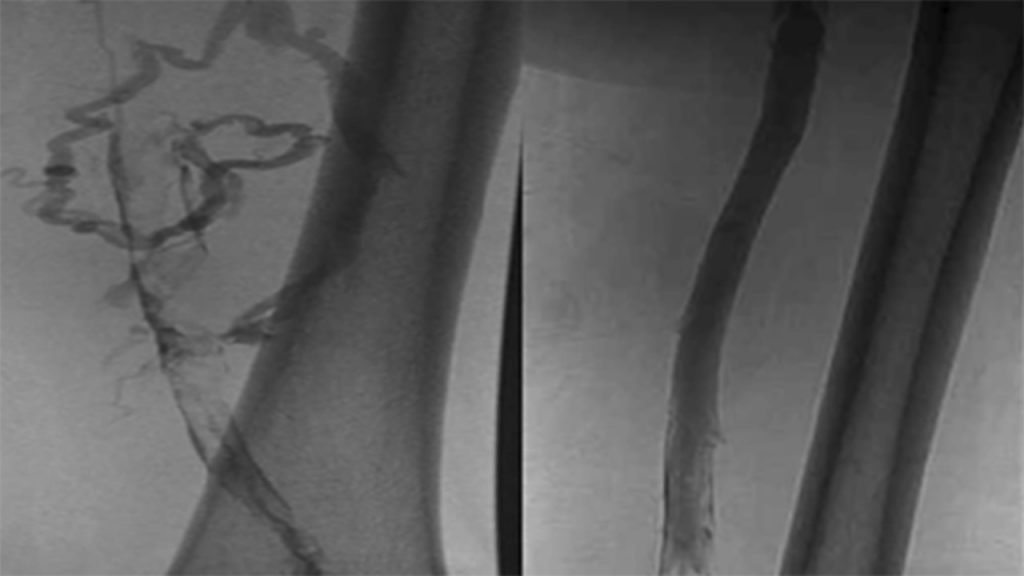

Photos of Diagnostic Procedures

Despite serious complications, DVT can be treated if detected early. Certain treatments may work for some patients, but not others. A vascular specialist may recommend treatments that prevent the blood clot from enlarging and moving to the lungs or other therapies to dissolve the clot right away. These treatments may include:3 Photos of DVT Treatments

Deep venous insufficiency can encompass a blockage of a vein upstream or downstream resulting in an insufficiency of flow. Photos of Diagnostic Procedures

Photos of DVI Treatments